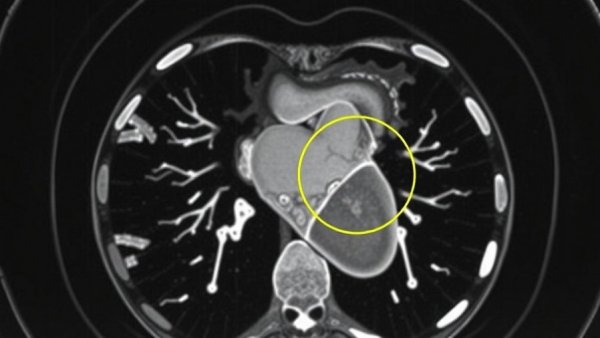

CT scan image highlighting AI-powered cardiovascular screening in Michigan.

In an inspiring stride towards enhancing cardiovascular health, McLaren Health Care has launched the first AI-powered cardiovascular screening platform in Michigan. This innovative tool aims to identify patients at risk for heart disease by analyzing chest CT scans conducted for non-cardiovascular reasons. Developed in partnership with Bunkerhill Health, this initiative promises to catch potential heart issues before they escalate, significantly improving patient outcomes.

A Peek Behind the Technology

The new AI-driven technology functions by sifting through chest CT scans that may have originally been ordered due to unrelated concerns, such as trauma or pneumonia. Dr. Samar Kazziha, chief medical director at McLaren Heart and Vascular Institute, underlines its significance, stating, "This is a very important way of finding the disease before it causes any problems for the patient long-term or short-term." This tool, known as Carebricks and developed at Stanford University, taps into advanced algorithms to detect indicators of two prevalent forms of heart disease: coronary heart disease and aortic stenosis.